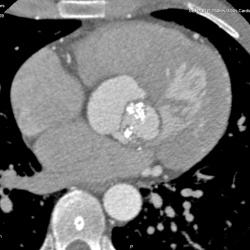

Недавно Сергей Николаевич выставлял бикуспидальный клапан. У него, как я помню, были некоторые сомнения, так как он раньше его не встречал. У меня также есть...